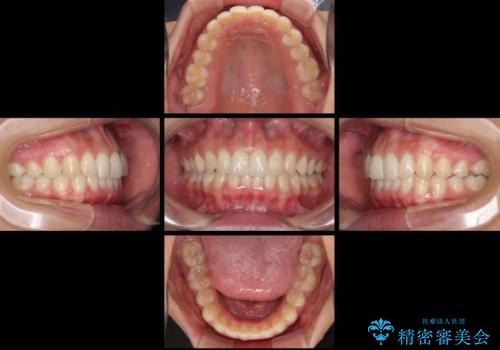

- 深い咬み合わせ(ディープバイト)と前歯のデコボコを気にして来院された患者様です。

インビザラインによる上下歯列の側方拡大と後方移動、IPR(歯と歯の間を削る)にるスペースの獲得により、デコボコとディープバイトを改善することとしました。

1日22時間の装着時間をしっかり守ってくださったので、予定通り1年で治療を終えることができました。

ディープバイトによる食いしばり癖も解消され、患者様には大変満足していただきました。